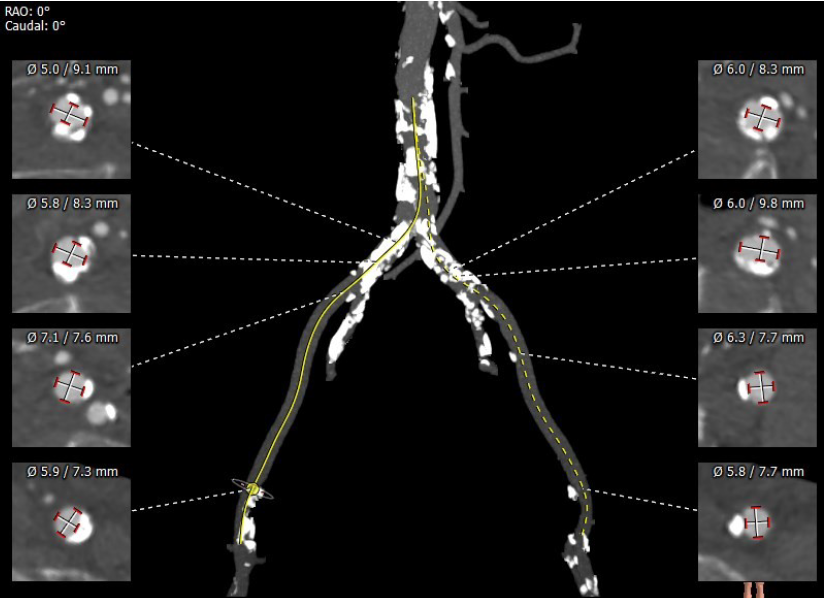

主动脉弓部走行较平缓,弓顶部可见少许钙化,主动脉弓部三根毛开口未见明显狭窄征象、未见发育变异,胸主动脉、腹主动脉走行较平直、腹主动脉多发严重钙化斑块,管腔未见明显狭窄,双侧髂动脉-股动脉走形迂曲,双侧髂动脉多发严重钙化斑块,部分呈半环形、马蹄形分布,右侧股动脉可尝试做为主入路,左股动脉作为脑保护入路。虚拟瓣环直径25mm,左室流出道平均直径23.3mm,拟植入VenusA Plus 23/26号的瓣膜。术中balloon sizing确认瓣膜型号,同时确认冠脉风险。

考虑脑保护装置偏转过滤器需完全覆盖主动脉弓部三条血管,无法再常规通过桡动脉进行冠脉保护,为此,周玉杰教授团队在术前进行了充分的讨论,决定在左侧股动脉穿刺两条入路分别进行冠脉保护和脑保护,患者腹主动脉到双侧髂动脉均有多发钙化斑块,可能会影响大鞘、脑保护及冠脉保护器械的操作,因此周院长特意准备了长鞘,必要时可将冠脉保护器械直接跨过腹主动脉,便于操作。